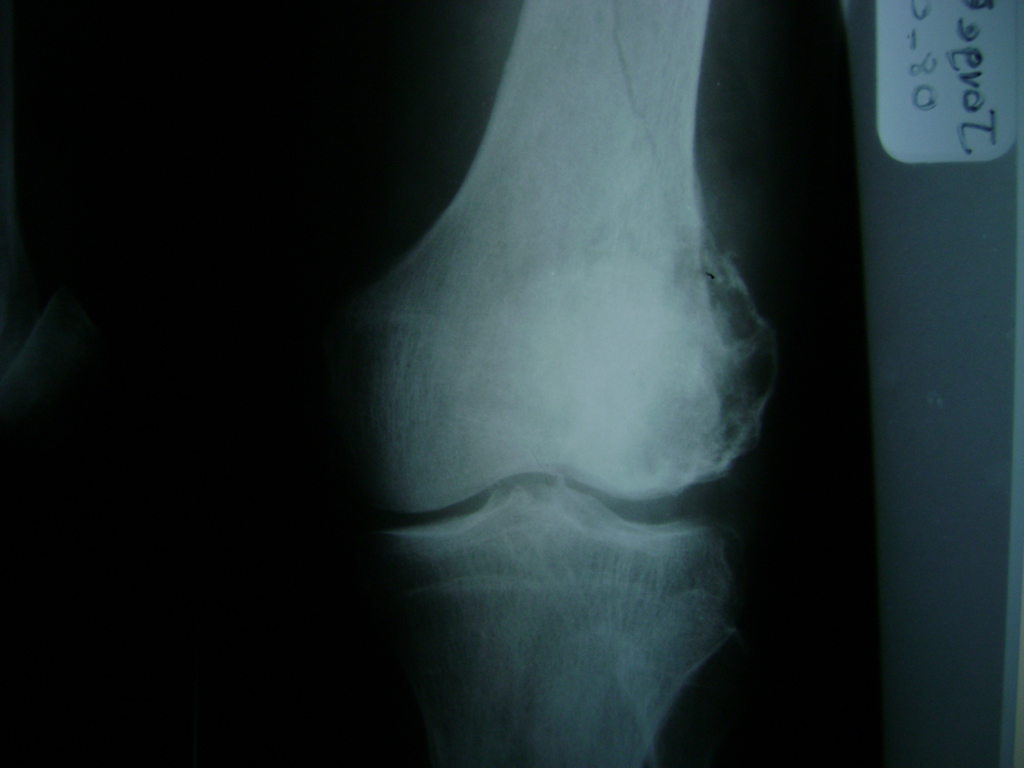

Cirugías de Codos - Rodilla

La artroscopia de rodilla es un cirugía en el cual la estructura interna de la articulación es examinada ya sea para realizar un diagnostico o para realizar un tratamiento, este procedimiento se realiza utilizando un instrumento parecido a un pequeño tubo llamado artroscopio.